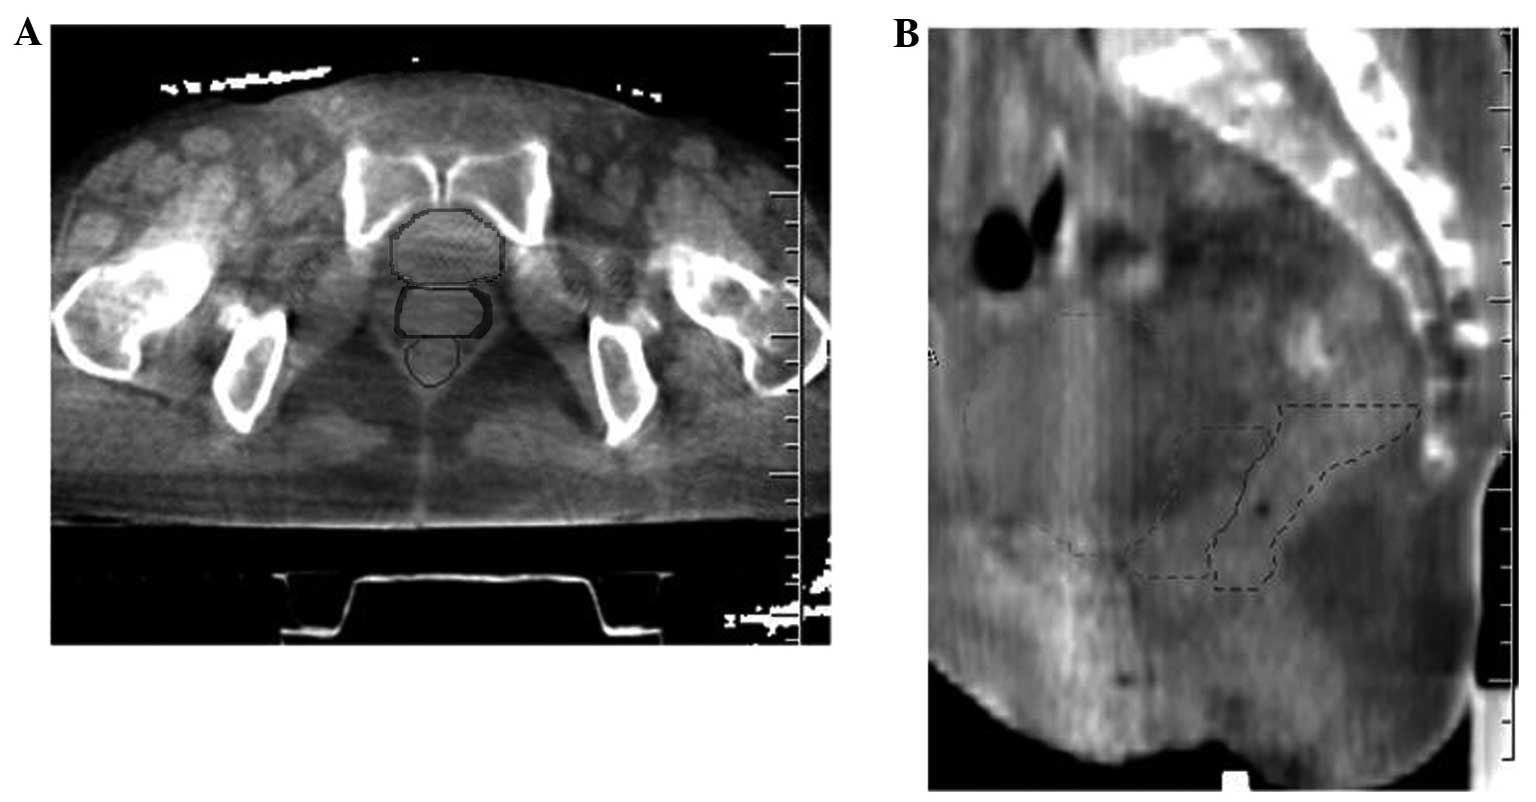

Interfractional variations of the bladder, rectum and vagina may affect the accuracy of postoperative intensity‑modulated radiotherapy in patients with cervical cancer. This study aimed to assess the interfractional variations with daily kv cone‑beam computed tomography (CBCT). All the patients were instructed to control the filling status of the bladder and rectum. CBCT images were obtained daily after set‑up and the bladder, rectum and vagina were contoured on each CBCT scan. All the contours were transferred to the planning CT following image fusion. Interfractional variations in pelvic organs were assessed with CBCT based on two reference lines, which were identified as A (the midsaggital line across the superior border of pubic symphysis) and B (a parallel line 1.5 cm above line A). The mean volume (range) of the bladder and rectum was 156.5 (1.7‑626.5) and 48.2 (11.3‑139.7) ml, respectively. The uniform planning target volume (PTV) margin of 10 mm failed to encompass the vagina in 17.3 and 18.1% of the fractions on lines A and B, respectively. The motion of the vagina (standard deviation) was 0.3 (0.3) and 0.1 (0.5) cm on lines A and B, respectively. The anteroposterior dimension and position of the vagina were significantly affected by the filling status of the bladder (P<0.05), but not by that of the rectum. Although instructions were given, the interfractional variations of the vagina and other pelvic organs were significant, which may exceed the uniform PTV margin; therefore, more effective methods to decrease these variations should be investigated.